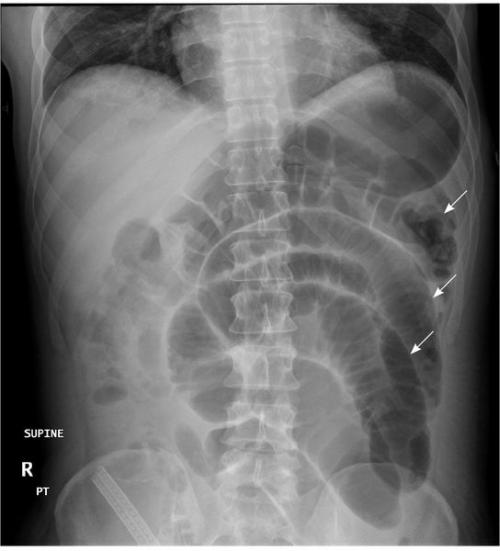

Рентгенологические признаки ОКН:

- чаши Клойбера;

- симптом перистости;

- кишечные аркады.